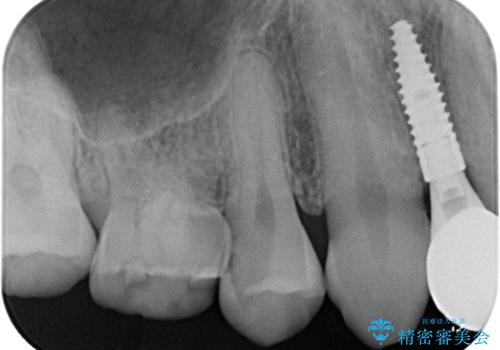

- 「歯がたまに痛む」を主訴に来院された患者様です。 見た目では齲窩が無いように見えますが、レントゲンを撮ると神経の近くまで達する深い虫歯だとわかりました。

虫歯を除去後セラミックインレーで治療を行いました。隣の子どもの歯のEも虫歯になっていたので同時に治療を行いました。

神経の近くまで虫歯が広がっていましたが、神経を保存して治療を行うことが出来ました。

見た目も凄く綺麗になり痛みも無く経過も良好なので、患者様も大変ご満足されていました。

Eに関してはCRで修復を行っています。